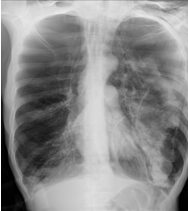

âȘ Table 5: We visualize samples of the generated reports for three cases. We bold the identical descriptions, underline the additional identified findings, and in red the failure findings..

X-ray Image | Baseline | M2TR | R2Gen | Ours |

![]() |

Pneumothorax gauche de moyenne abondance./Silhouette cardiaque dâaspect normal./Absence dâanomalie mĂ©diastinale./Absence dâĂ©panchement pleural./Absence dâanomalie du gril costal./ | Pneumothorax gauche de grande abondance./Contours cardiaques rĂ©guliers./MĂ©diastin sans anomalies dĂ©celables./ Aucun Ă©panchement pleural dĂ©tectĂ©./Structure du gril costal normale. | Pneumothorax de petite abondance./Aucune anomalie visible au niveau du mĂ©diastin./Pas de prĂ©sence d'Ă©panchement pleural./ | Pneumothorax bilatĂ©ral de moyenne abondance./Configuration normale de la silhouette cardiaque./MĂ©diastin clair, sans irrĂ©gularitĂ©s./Absence d'Ă©panchement pleural./Aucune lĂ©sion du gril costal observĂ©e./ |